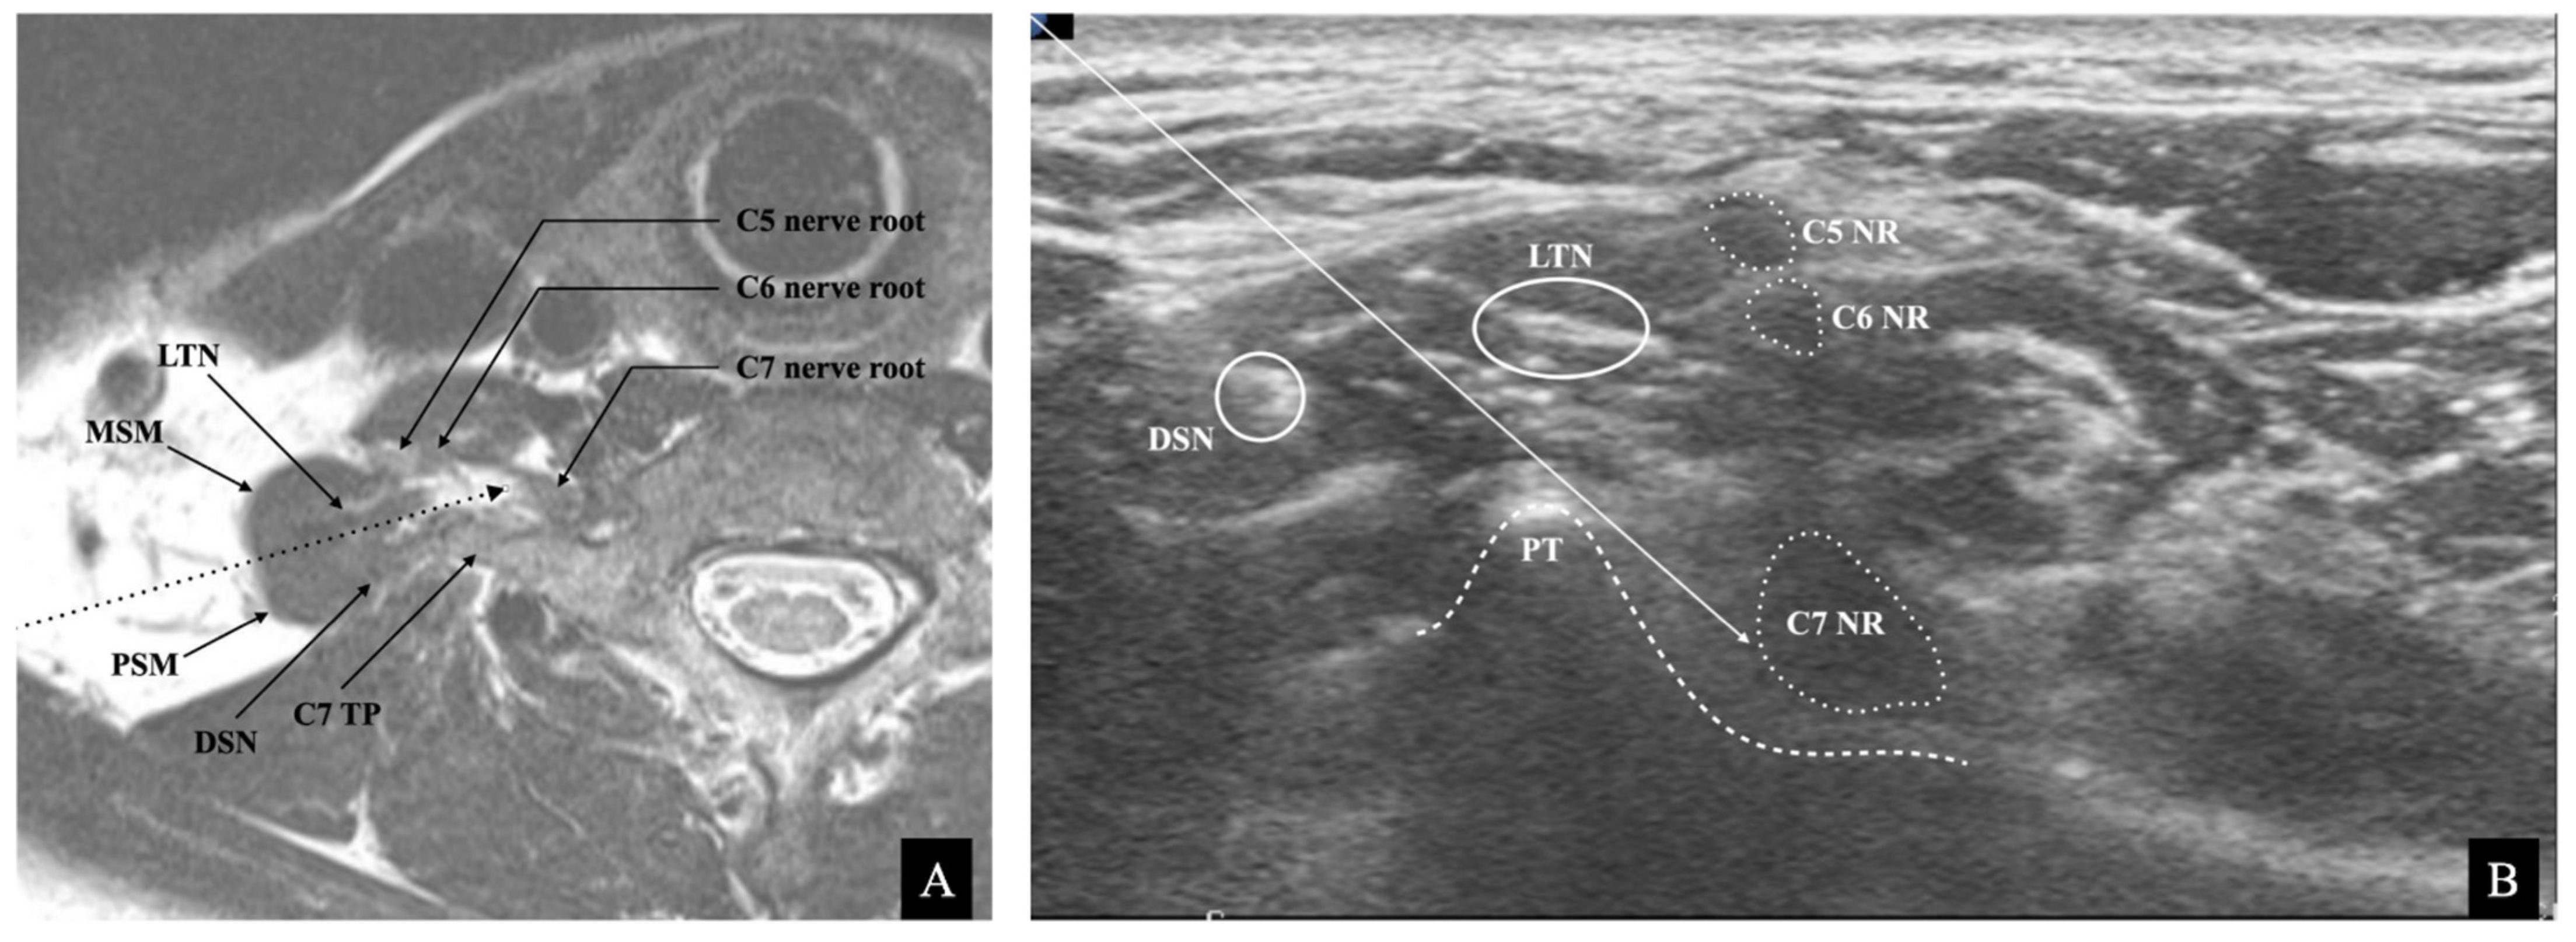

2.1. Ultrasound Image

- Hanson, N.A.; Auyong, D.B. Systematic ultrasound identification of the dorsal scapular and long thoracic nerves during interscalene block. Reg. Anesth. Pain Med. 2013, 38, 54–57. [Google Scholar] [CrossRef] [PubMed]

- Chang, K.V.; Wu, W.T.; Mezian, K.; Nanka, O.; Ozcakar, L. Sonoanatomy revisited: The long thoracic nerve. Med. Ultrason. 2019, 21, 349–352. [Google Scholar] [CrossRef] [PubMed]